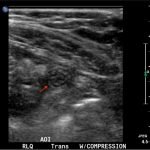

In the long axis video, the appendix appears as an enlarged, non-compressible, blind-ending tubular structure (white arrow) with distinct appendiceal wall layers and lack of peristalsis. In the short axis video, the appendix appears as a target sign (yellow arrow) between the abdominal and psoas muscles. The maximal outer diameter (MOD) measures 11.8mm and the appendix wall measures 0.17mm. There is trace adjacent free fluid and echogenic periappendiceal fat. Transverse axis video and image (red arrow) demonstrate that the appendix is not compressible. These findings are consistent with acute appendicitis.